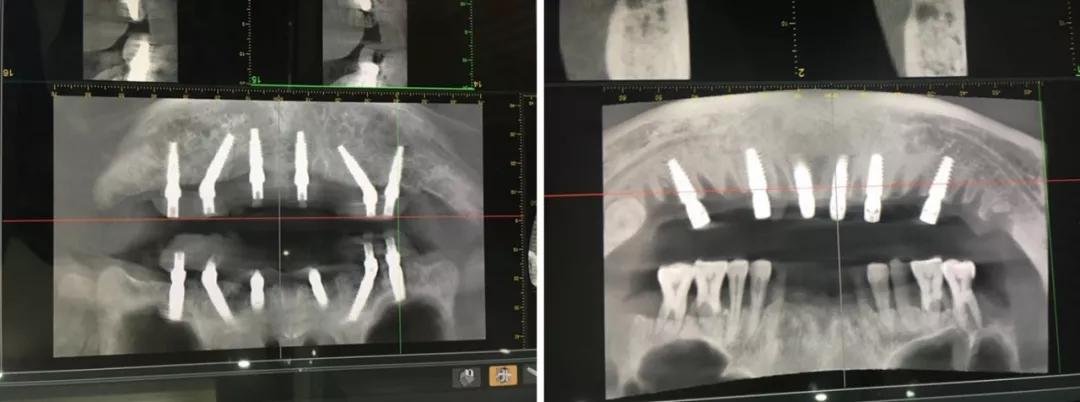

日照口腔医院种植中心配置先进的种植手术室,为患者提供各种类型的种植义齿修复,在日照市最早开展口腔种植技术,采用先进的医疗技术装备和世界一流的种植系统,配备有丹麦3shape口内扫描仪、Yoshida激光治疗仪、卡瓦(KaVo)锥形束CT、超声骨刀等国际先进仪器和设备,装备有瑞士士卓曼等多套国际种植系统,同时配备国际一流的消毒供应室,为疑难复杂病例的诊治提供了必要条件。

医院开展CAD/CAM数字化种植导板技术,通过整合数字化影像、cbct 数据以及数字化加工技术的新型种植导板,充分考虑到了颌骨条件、口腔解剖结构以及修复效果的结合,且精确度高,手术安全性高。